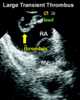

Intracardiac thrombus